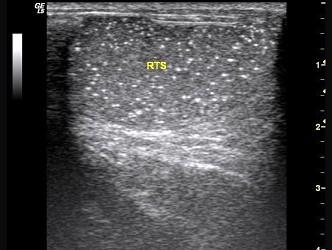

超声示双侧睾丸内见多个点状强回声光斑,弥漫性分布。如图所示,考虑为 ?(?)A.睾丸囊肿B.睾丸结石C.睾丸结核D.睾丸微石征E.睾丸附睾炎

问题 超声示双侧睾丸内见多个点状强回声光斑,弥漫性分布。如图所示,考虑为 ?(?)

选项 A.睾丸囊肿 B.睾丸结石 C.睾丸结核 D.睾丸微石征 E.睾丸附睾炎

答案 D